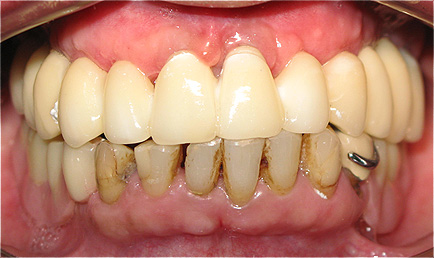

Resultado de colocação de implante dentário na Clínica São Filinto

A colocação de implantes dentários de titânio é, atualmente, a melhor forma de substituir os dentes ausentes, pois não só lhe devolve a estética dentária perdida, como também a sua função mastigatória.

A utilização de novos materiais nas coroas implanto-suportadas, como o zircónio, e as novas técnicas laboratoriais avançadas, em conjunto com a utilização de softwares especializados na construção das coroas dentárias, aumenta ainda mais a estética dentária porque confere ao dente um aspeto muito natural.